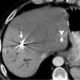

Liver tumor embolization

Liver cancer (also known as hepatic cancer, primary hepatic cancer, or primary hepatic malignancy) is cancer that starts in the liver. The word "hepatic" is from the Greek hêpar, meaning "liver". [Source: Wikipedia ]